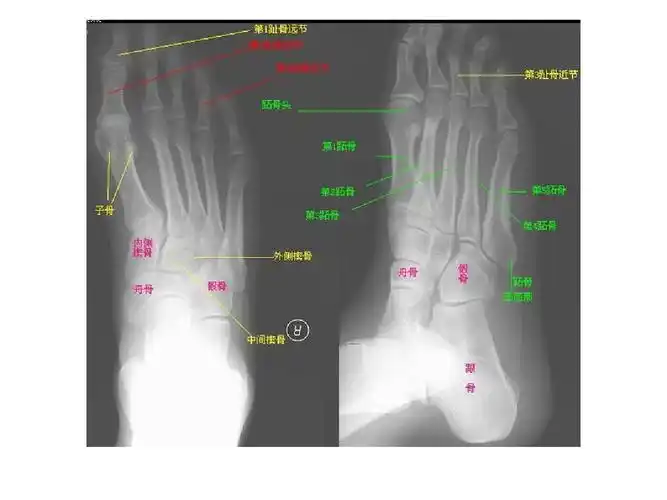

x线解剖(绝版收藏) - 医行博客 - 龙氏正脊的追随者---王世臣的博客

收藏骨关节系统x线解剖图谱

x线解剖图谱系统解剖骨骼篇非常全面强烈建议收藏

足侧位x线解剖图